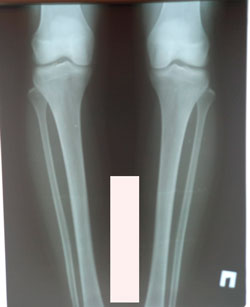

Исходник - 36 лет.

Дата операции - 03.02.2021

image-18-02-21-05-31-1.jpg

image-03-02-21-12-29.jpg